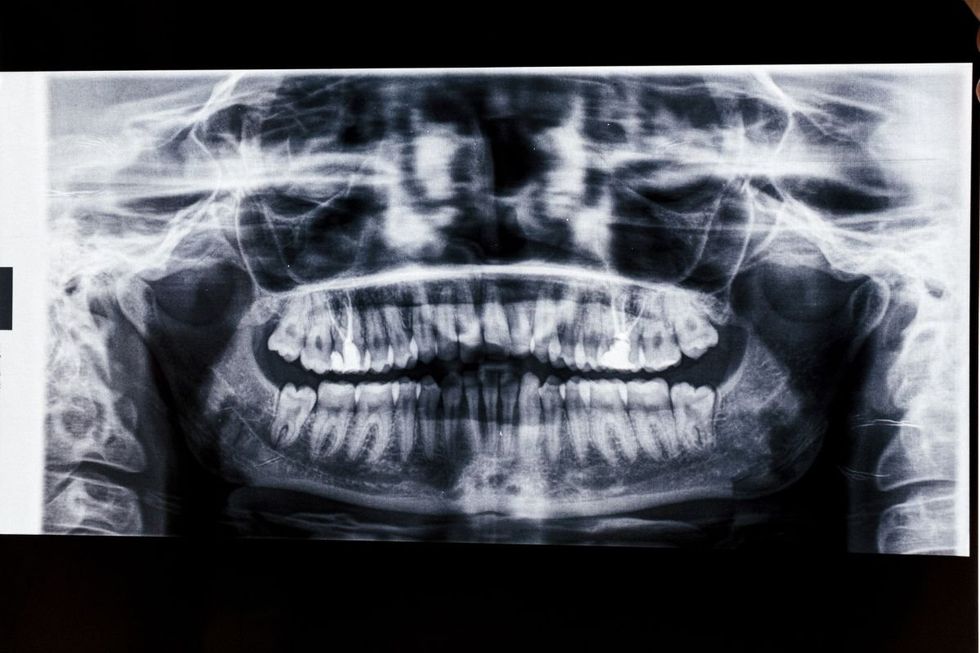

ESCANEAMENTO DE CÂNCER ORAL

Os sintomas que requerem investigação são dificuldade para engolir e dor persistente